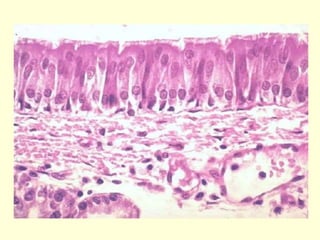

• En la neumonía bacteriana

representada en la imagen se aprecia

un corte histológico de alvéolos

pulmonares normales (arriba)

comparados con alvéolos durante una

neumonía. Se puede ver cómo están

llenos de células inflamatorias y de

abundante infiltrado.